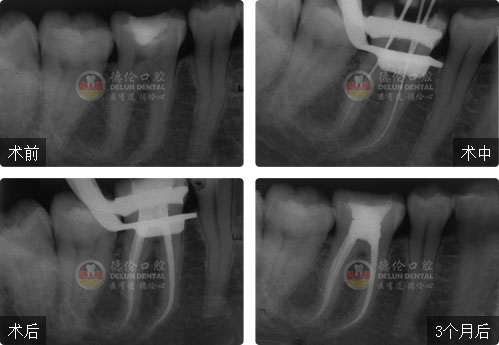

• 性別:

年齡:26歲

牙齒癥狀:急性牙髓炎(左下爛牙近一周自發性、陣發性疼痛)

治療方法:顯微根管治療

疑難點評:填充嚴密、各根管均恰填,高質量地完成了彎曲根管和S形根管的治療,體現操作者優秀的臨場操作能力。